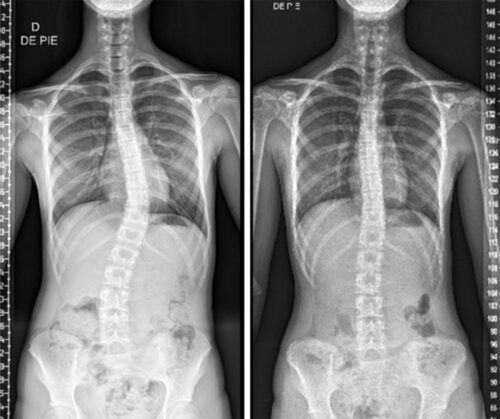

اعوجاج العمود الفقري بعد أول دورة شهرية:هل يستمر أم يتوقف؟

عندما تُصاب الفتاة باعوجاج العمود الفقري في سن المراهقة، يكون من أول الأسئلة التي تدور في ذهن الأهل: هل سيزداد الانحناء بعد بدء الدورة الشهرية؟ وهل تعني الدورة أن مرحلة الخطر قد انتهت؟

بداية الدورة الشهرية علامة مهمة في نمو الفتاة، لكنها لا تعني بالضرورة اكتمال نمو العظام أو توقف اعوجاج العمود الفقري. فهم العلاقة بين الدورة الشهرية ومرحلة النمو يساعد الأهل على اتخاذ قرارات صحيحة بشأن المتابعة والعلاج.

تحدث أول دورة شهرية عادة بعد فترة قصيرة من ذروة طفرة النمو السريع. في السنة التي تسبق الدورة يكون الجسم في أسرع مرحلة زيادة في الطول، وهي أيضًا المرحلة التي يكون فيها خطر زيادة انحناء العمود الفقري في أعلى مستوياته.

بعد بدء الدورة الشهرية، يبدأ معدل النمو في التباطؤ تدريجيًا، لكنه لا يتوقف فورًا. غالبًا تستمر الفتاة في زيادة الطول لمدة سنة إلى سنتين بعد أول دورة، ما يعني أن العمود الفقري لا يزال في مرحلة نمو.

لهذا السبب، لا يمكن اعتبار الدورة الشهرية نقطة نهاية للخطر، بل بداية مرحلة انتقالية يقل فيها الخطر تدريجيًا.

إذا كانت زاوية الانحناء صغيرة ومستقرة، فغالبًا لا يحدث تطور كبير بعد الدورة. أما إذا كانت الزاوية متوسطة أو كبيرة، فقد تستمر الزيادة لفترة محدودة، خاصة إذا بقي نمو واضح في الطول.

اعوجاج العمود الفقري بعد الدورة الشهرية لا يتوقف تلقائيًا في جميع الحالات، لكنه غالبًا يدخل مرحلة أكثر استقرارًا مع تباطؤ النمو. الدورة الشهرية علامة مهمة تشير إلى اقتراب اكتمال النمو، لكنها لا تعني نهاية المتابعة.